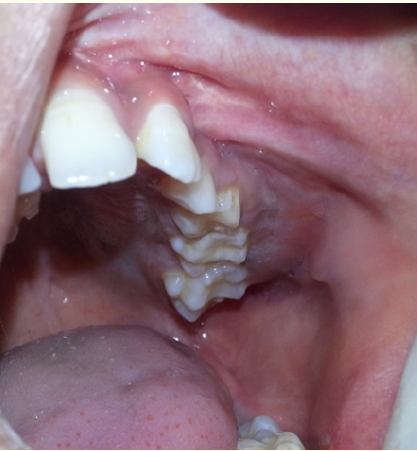

Case Report

Segmented Arch Versus all on 4 Implant Design: A Case Report of Severe Bite Object